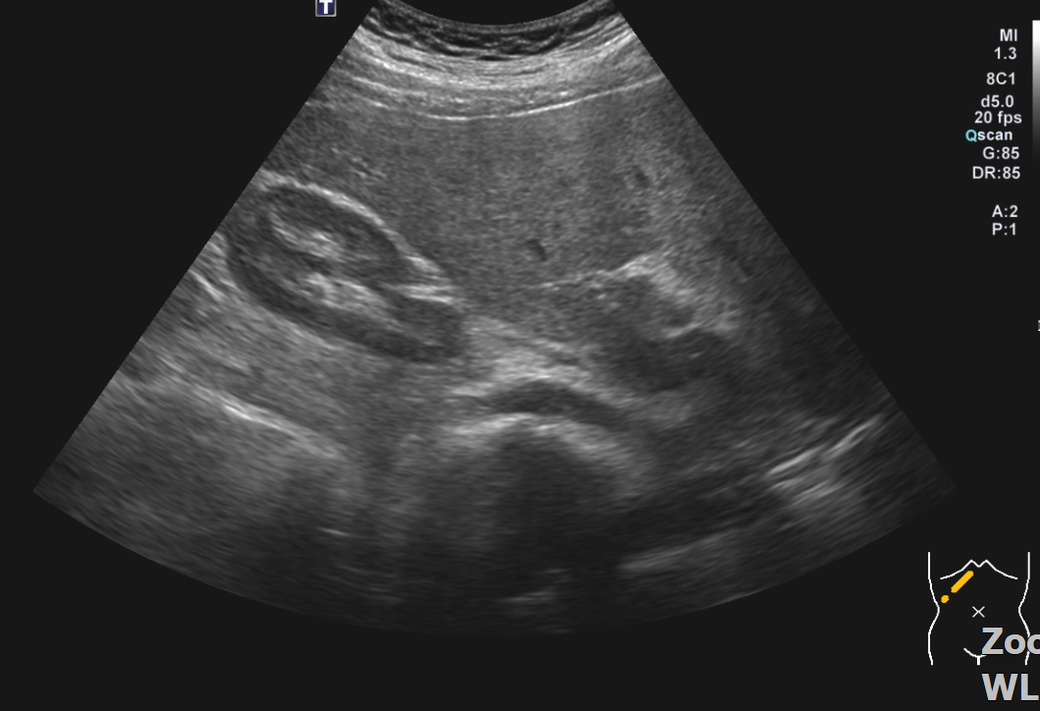

뭐가보이나요? 부위 사진 캡쳐하고 4장 같은부위 촬영사진 올려요

• 2번 째 사진